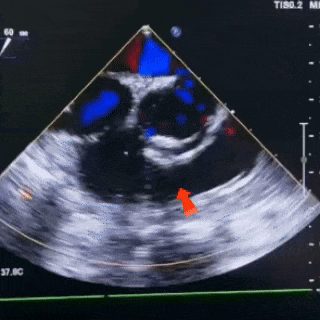

右盘展开

固定钢缆,后撤鞘管,展开右盘

锁定前观察

双盘展开后,封堵器骑跨于室间隔

彩色血流显示无残余分流